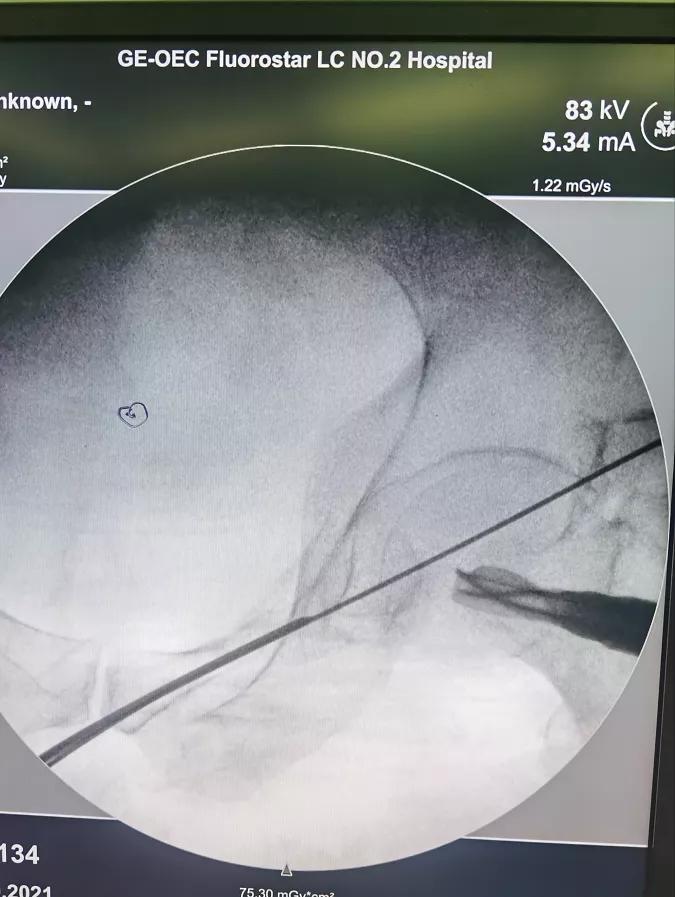

病人王**,男性,78岁,因摔伤致骨盆前后环骨折入院,患者手术意愿强烈,鉴于患者年龄较大,经科室内讨论,决定给予患者闭合复位经皮微创骶髂螺钉、耻骨支螺钉内固定术,在刘德强主任的指导下,都芳涛、方继锋、范孟坡、刘斌医师治疗团队,结合患者术前影像学资料,精确规划进钉点、进钉角度,在腰麻下进行手术治疗,术中反复进行C臂多角度透视,确定螺钉位于安全区内,顺利置入螺钉,术中出血约10毫升。目前患者在张来民护士长、路秀娥专职护师的精心护理下,恢复满意。

术中影像